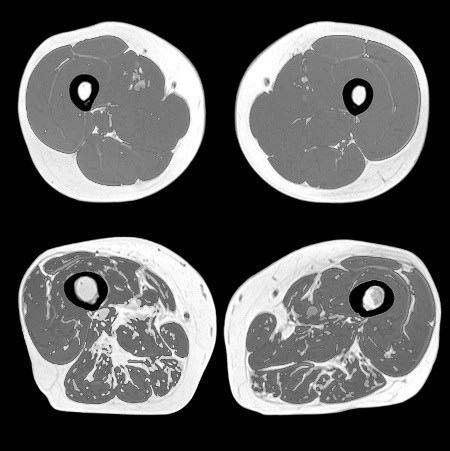

Здоровые рука и суставы. ![]() Рука с артритными суставами. Кроме того, старение приводит к дефициту проприоцептивных навыков – ощущения положения тела и ориентации в пространстве. Он возникает при снижении количества тензорецепторов в связках, из-за чего нарушается восприятие расположения суставов в пространстве. ![]() Старение суставного хряща приводит к воспалению и аномальному росту. Стареющие мышцы Саркопения – это термин, под которым подразумевают снижение массы скелетных мышц и их возможностей нормального функционирования. Этот прогрессирующий возрастной синдром сопряжен и с другими недостатками: снижением качества жизни и повышенным риском инвалидности и смерти. К потере мышечной массы приводит истончение миофибрилл внутри мышечных волокон, из-за чего снижается толщина самого волокна (чаще встречается у волокон 2-го, быстро сокращающегося типа). Миофибриллы атрофируются со скоростью от 3 % до 8 % в каждые 10 лет (в возрасте от 30 лет). А для людей старше 65 лет этот показатель еще больше возрастает. Потеря мышечной массы может быть связана c уменьшением количества самих волокон. В возрасте от 24 до 50 лет скорость атрофии мышечных волокон увеличивается с 5 % до 35 %. Считается, что возрастные изменения в нервно-мышечном соединении приводят к тому, что связанный с ним нейрон отделяется от мышечного волокна (лишается иннервации), а затем умирает в результате апоптоза (см. параграф «Запрограммированная гибель клетки: апоптоз» на стр. 51). ![]() На этих МРТ-снимках изображены бедра здорового 31-летнего мужчины (вверху) и здорового 81-летнего мужчины (внизу). Потеря мышечной массы и увеличение фиброзно-жировой ткани – характерные признаки саркопении. Процесс старения не щадит и сателлитные клетки, которые в норме отвечают за восстановление поврежденных мышц. С возрастом их популяция сокращается на целых 50 %. ![]() Считается, что танцы – это увлекательный способ замедлить или обратить вспять процесс потери скелетных мышц. Кроме того, у пожилых людей танцы улучшают здоровье мозга. На работоспособность мышц влияет и тип разрушенных мышечных волокон. Оказывается, что старение приводит к потере двигательных нейронов, которые иннервируют 2-й тип мышечных волокон, быстро сокращающихся. Такое изменение не только уменьшает количество волокон, но и способствует тому, что некоторые волокна начинает иннервировать 2-й, медленно сокращающийся тип двигательных нейронов. Это, в свою очередь, изменяет скорость реакции, удельную мощность мышц, их координацию и силу. Мышечная архитектура страдает и из-за разрастания фиброзно-жировой ткани. Все это накладывается на сопутствующие возрастные изменения и влияет на динамику мышечно-костных отношений. В результате снижается действенность упражнений, направленных на увеличение мышечной силы и костной массы. Многие исследователи говорят, что скорость потери мышечной массы можно компенсировать регулярными упражнениями (особенно танцами), поэтому пословица «движение – жизнь» глаголет истину. |